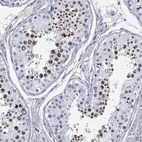

Immunohistochemical staining of human testis shows strong nuclear positivity in cells in seminiferous ducts.